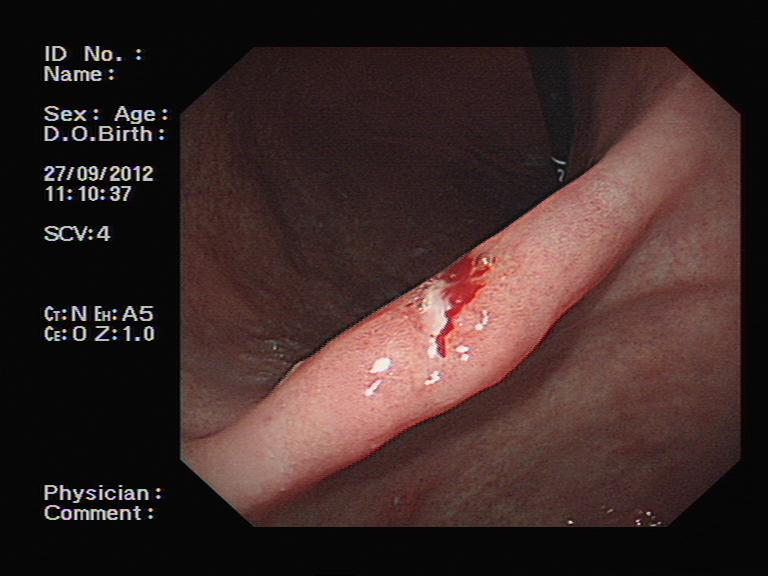

这是一名外地来京求医的中年女性。她因为严重腹痛在当地医院就诊,胃镜检查后诊断为“胃角溃疡”,活检提示“重度异型增生”,给予相应治疗后患者仍然有剧烈腹痛,来到我院消化内科就诊复查胃镜。

胃镜检查证实了胃角部位的一处不大的溃疡,我们再次进行了活检。不过,意想不到的是,当检查医师进镜至十二指肠时,吃惊地发现十二指肠球部有一个正在蠕动的白色圆柱状物体,这是什么呢?原来是一条蛔虫,头端还在十二指肠降部,尾端留在了球部。见状,蔺武主任医师反复尝试,最终用圈套器取出了蛔虫。患者家属很高兴,因为找到了腹痛的原因,那么,事情结束了吗?检查之后病理很快回报:患者的胃溃疡活检标本中存在局部癌变,该患者的胃角溃疡为早期胃癌。

内镜下可见胃角浅小溃疡